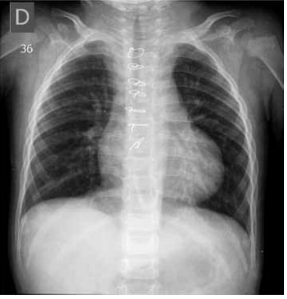

Paciente de 1 mês de idade foi admitido em Unidade de Terapia Intensiva, acompanhada de cuidadora de abrigo, devido à piora da cianose. Mãe drogadita perdeu guarda dos 6 filhos. A saturação na Unidade manteve-se estável, ao redor de 84%, sem insuficiência cardíaca congestiva, em uso de propranolol; foi acompanhado no ambulatório até os 2 anos de idade e realizada intervenção cirúrgica cardíaca. Com base nos seguintes exames complementares, quais seriam, sucessivamente, a cardiopatia congênita provável, a cirurgia realizada aos 2 anos de idade e a cirurgia atual para a qual foi convocada?

(Arquivo pessoal; imagens usadas com autorização)